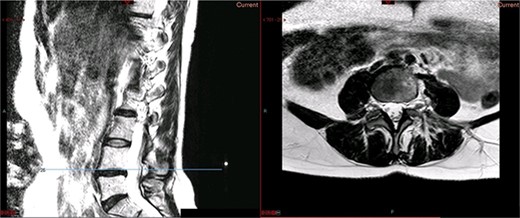

A magnetic resonance imaging (MRI) scan performed in October 2013 (Fig. 1) identified non-compressive, degenerated discs at L4/5 and L5/S1 vertebral levels. However, clinically as the patient was more tender over the left SI joint and the pubic symphysis (Fig. 2), a left sacroiliac joint fusion and symphysis pubis plating procedure was performed in August 2014 (Fig. 3). Following a short period of relief, the pain returned. Subsequently, the patient underwent a 360° fusion (front and back) of the L4/L5 and L5/S1 discs in August 2015 (Fig. 4), a year following the previous surgery. Once again, following a brief period of relief, the symptoms returned. The assumption then was that the initial fusion of the left sacroiliac joint had failed. Therefore, a revision fusion of the left sacroiliac joint and a primary fusion of the right sacroiliac joint was undertaken in August 2017 (Fig. 5).

Preoperative MRI scan of the lumbar spine: preoperative MRI scan of the lumbar spine performed in October 2013, showing non-compressive disc degeneration at the L4/5 and L5/S1 vertebrae.